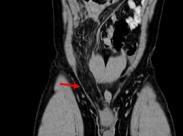

大網膜扭轉

• 大網膜扭轉

628健康網為您分享有關大網膜扭轉的癥狀,大網膜扭轉的治療方法,大網膜扭轉的預防知識,大網膜扭轉的癥狀圖片,大網膜扭轉...